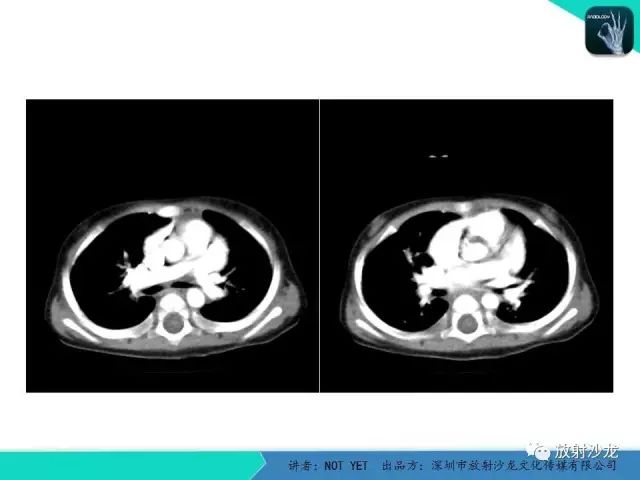

动脉导管未闭1例CT影像表现

【病例】动脉导管未闭1例CT影像表现